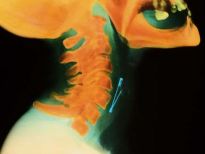

Bu röntgenler gerçek!

Bu röntgenler gerçek! galerisi resim 1

İki çatalı, bir tükenmez kalemi ve diş fırçasını yutmuş bir hasta.